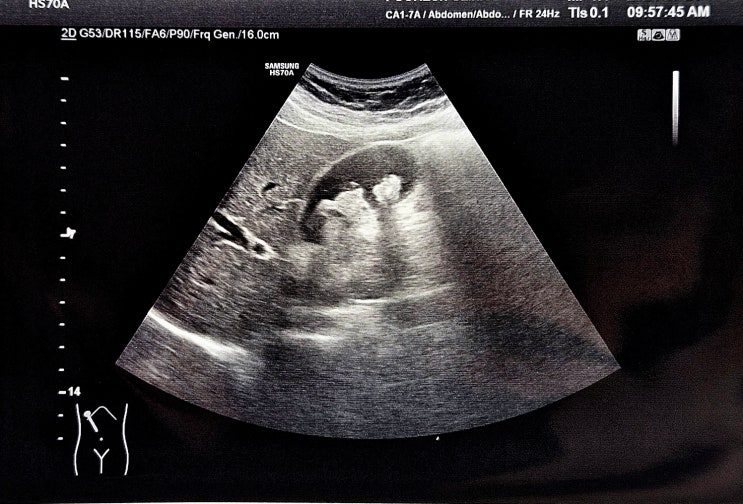

복통을 동반 한 담석증 45세 여자. 밤새 윗배가 아팠다며 내원. 특히 잠을 못잘정도로 많이 아팠다고 한다....